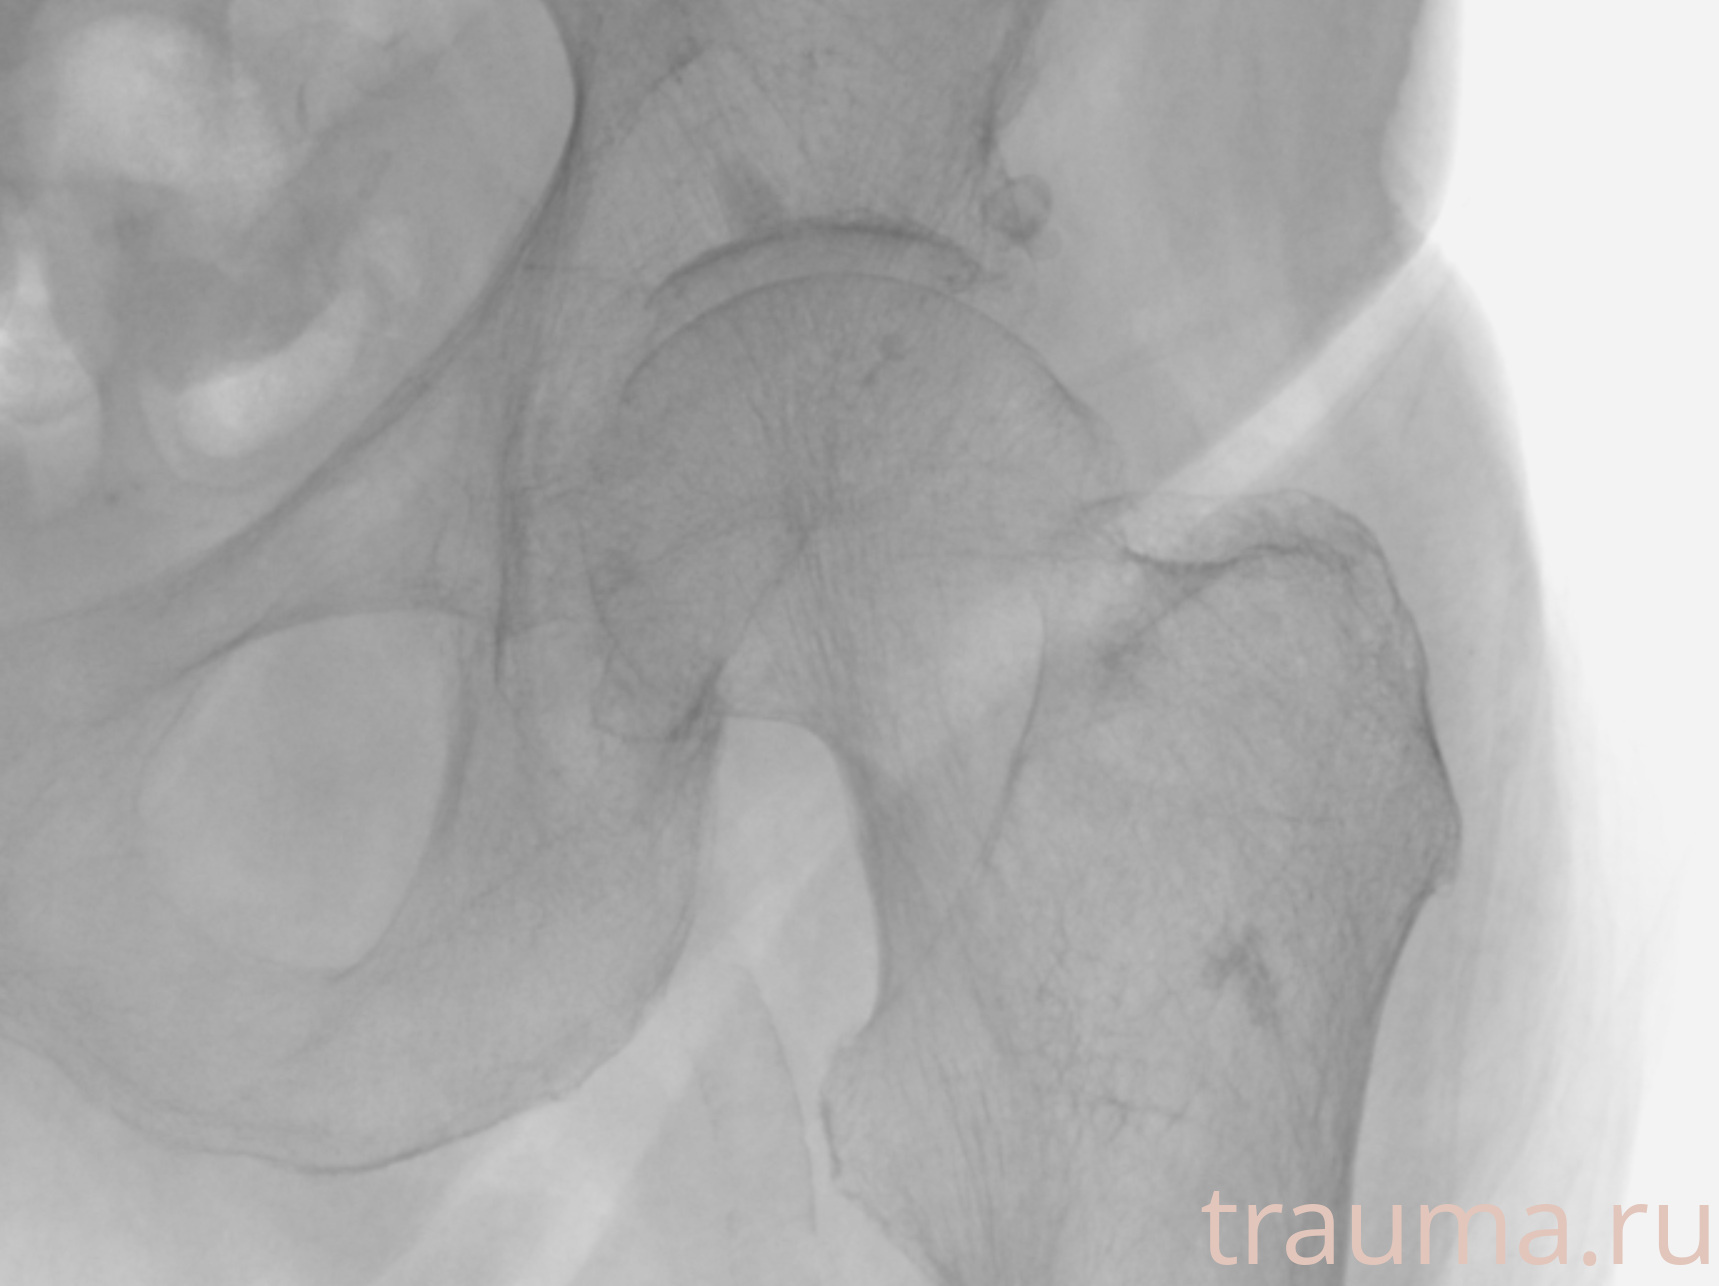

Рентгенограммы

Рентген на дому: по вашему адресу приезжает врач-рентгенолог, травматолог-ортопед с мобильным рентгеновским аппаратом, проводит диагностику травмы или заболевания, делает необходимые рентгенограммы, дает рекомендации по дальнейшему лечению. Получить качественные снимки в домашних условиях возможно благодаря уникальной методике, разработанной МосРентген Центром для института  Склифосовского